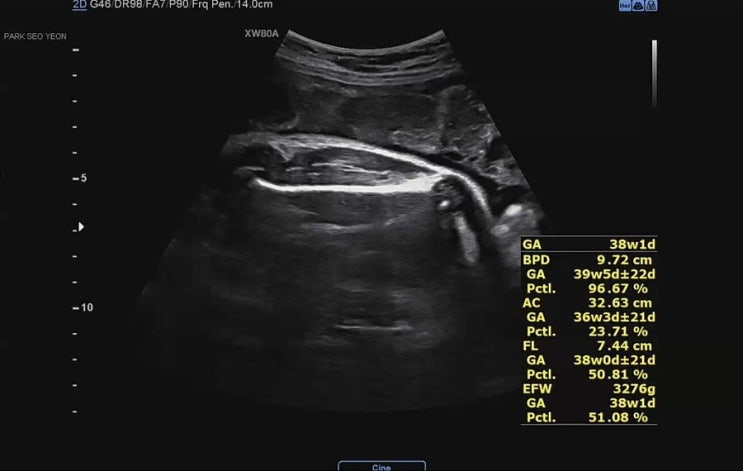

[태교일기] 임신38주차 | 태동검사 | 유도분만 날잡기